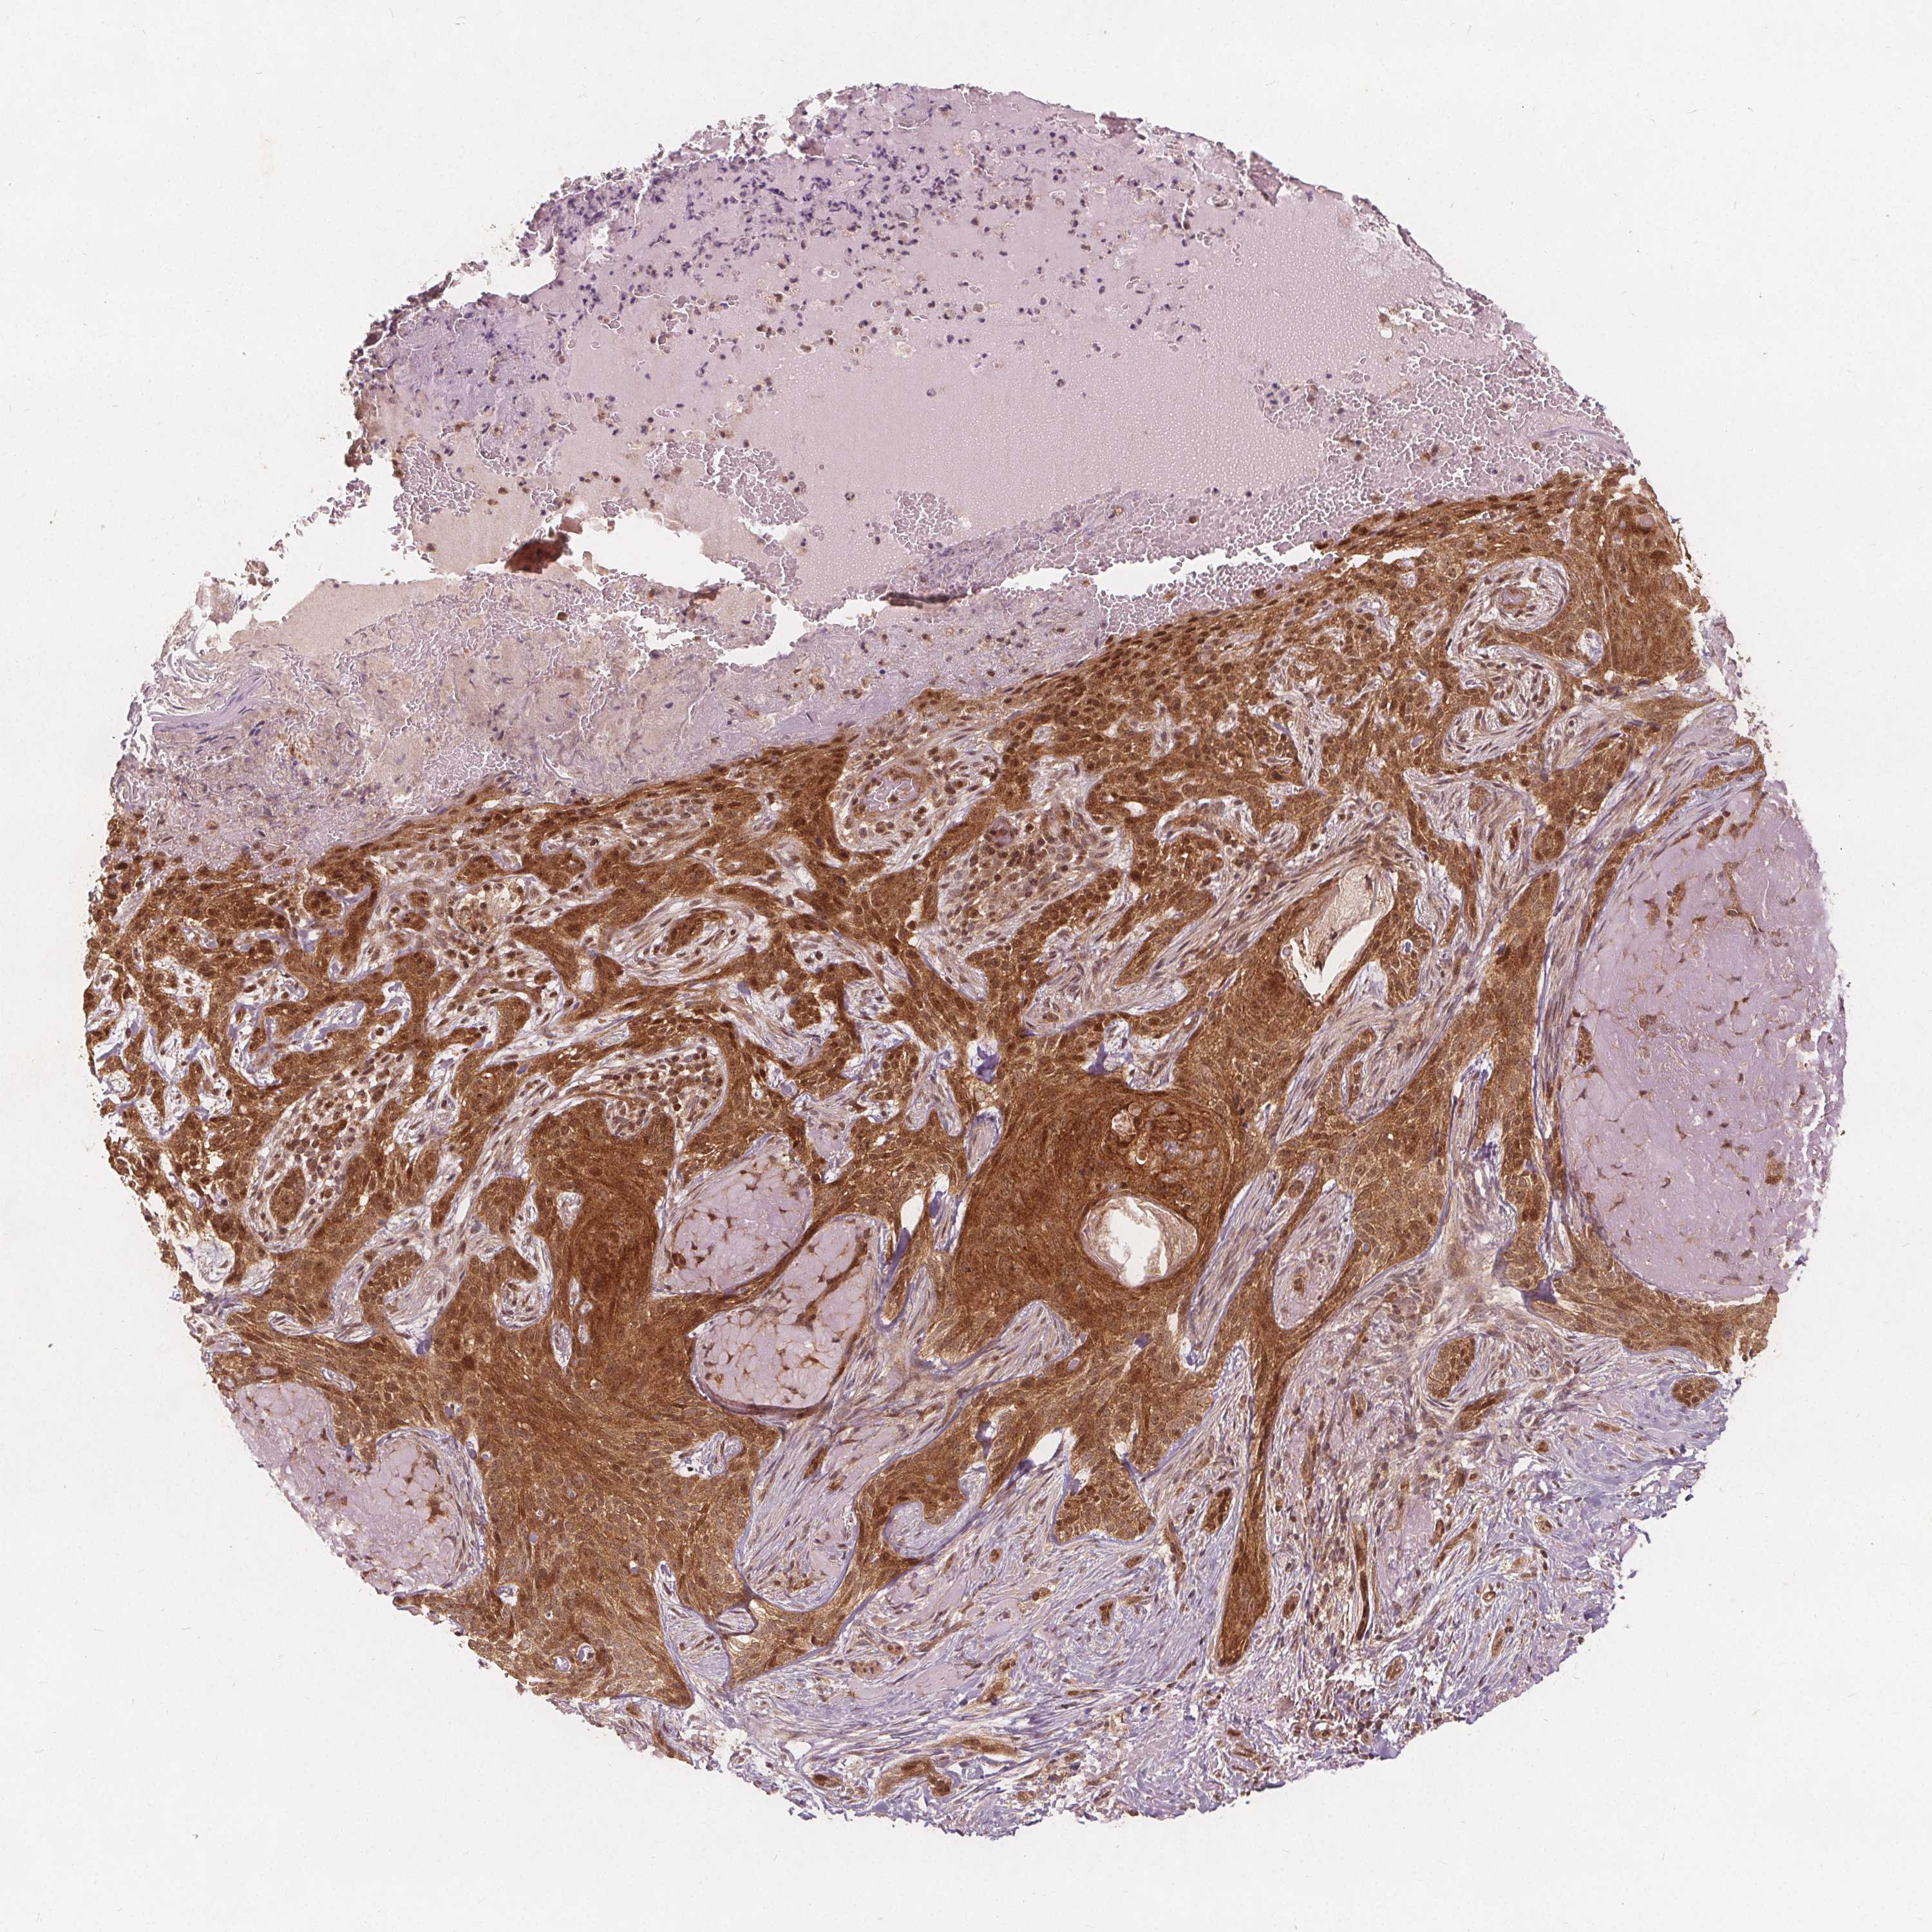

SKIN CANCER - Protein expressioni

A mouse-over function shows sample information and annotation data. Click on an image to view it in a full screen mode. Samples can be filtered based on level of antibody staining by selecting one or several of the following categories: high, medium, low and not detected. The assay and annotation is described here.

Antibody staining in the annotated cell types in the current human tissue is reported as not detected, low, medium, or high, based on conventional immunohistochemistry profiling in selected tissues. This score is based on the combination of the staining intensity and fraction of stained cells.

Each image is clickable and will lead to virtual microscopy that enables deeper exploration of all samples and also displays staining intensity scores, fraction scores and subcellular localization as well as patient and tissue information for each sample.

Antibody HPA065425

Basal cell carcinoma

BCC, high aggressive